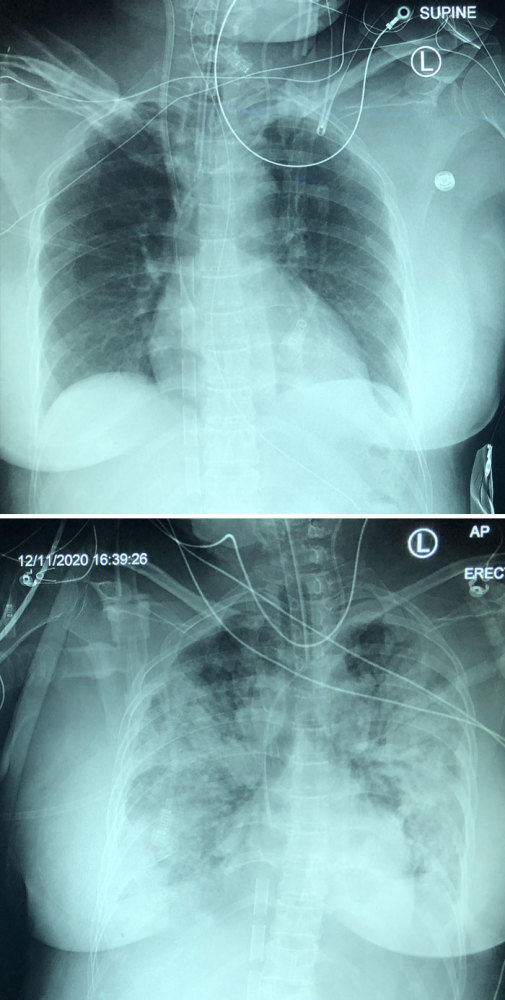

文章插图

covid肺炎的5天病情发展